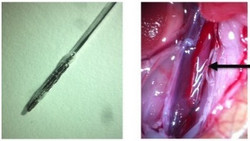

Najnowocześniejsze stenty uwalniają leki do najbliższych naczyń krwionośnych, aby zapobiec restenozie (ponownemu zwężeniu naczynia). Niestety te uwalniające leki stenty mogą przyczyniać się do formowania się skrzepów krwi i zakrzepicy w stencie. UE finansuje projekt the PRESTIGE(odnośnik otworzy się w nowym oknie) (Prevention of late stent thrombosis by an interdisciplinary global European effort) mający rozwiązać ten problem poprzez podejście interdyscyplinarne. Członkowie ogólnoeuropejskiego konsorcjum ulepszyli narzędzia diagnostyczne i zbadali techniczne środki przeciwdziałania lub zmniejszenia występowania zakrzepicy w stencie. Badacze skompilowali największy bank danych dotyczących przypadków zakrzepicy w stencie z wielomodalnymi ocenami z całego świata. Wstępne badania ujawniły nadspodziewanie duże rozpowszechnienie przyspieszonej miażdżycy w stencie w etiologii tych zdarzeń. Planowane są dalsze badania danych dotyczących konstruowania algorytmów czynników ryzyka. Do badań mechanizmów zakrzepicy i powłok, które mogą jej zapobiegać, a w szczególności najpowszechniej używanego materiału: stopu kobaltowo-chromowego, użyto dokładnego mysiego modelu stentu. Odkrycia wskazują, że materiał stentu może aktywować kaskadę koagulacyjną i w związku z tym należy przeprowadzić badania dodatkowych leczniczych strategii antykoagulacyjnych. Najskuteczniejsze metody obejmowały zastosowanie plazmy do obróbki powierzchni stentu, dołączenie peptydomimetyków do przyciągania komórek śródbłonka, chitosanowe powłoki polimerowe oraz bazujące na dekstranie kopolimery do korzystnego modulowania oddziaływań trombocyty-stent i szlaków koagulacji. W kolejnym etapie tętnice ze stentami, pozyskane od modeli miażdżycy u królików i od ludzi ex vivo, zostały użyte do stworzenia czułych algorytmów optycznego obrazowania do wykrywania niedojrzałych typów tkanki i miażdżycy wtórnej, często będących prekursorami późnej zakrzepicy w stencie. Innym kluczowym wynikiem był nowatorski cewnik do obrazowania bliską podczerwienią, specjalnie zaprojektowany do badań na zwierzętach. Odkryto, że komórki piankowate gromadzące się wokół wspornika stentu stanowią ważną cechę charakterystyczną tej choroby. W przypadku modelu zwierzęcego naukowcy byli w stanie wykryć różne ilości komórek śródbłonkowych w obrębie naczynia, ze słabszym sygnałem fluorescencyjnym w obszarach pozbawionej nabłonka aorty. Wyniki badania PRESTIGE wpłyną nie tylko na zmniejszenie obciążenia zakrzepicą w stentach. Ulepszone leczenie i diagnozowanie choroby tętnic wieńcowych serca wraz z nowymi technikami obrazowania, jak również skuteczniejsze leczenie stentami choroby naczyń mózgowych lub tętnic obwodowych, to tylko niektóre korzyści z tego projektu.